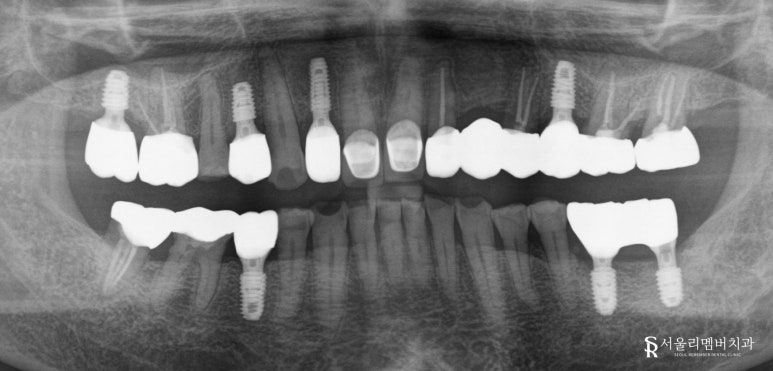

임플란트 가이드는 육안으로 확인할 수 없는

골조직이나 신경의 위치 등을 디지털 진단 장비를

통해 세밀하게 검사하는 것입니다.

이를 바탕으로 나온 결과를

모의 시뮬레이션을 진행하므로

구강 상태에 적절한 식립 위치나

깊이, 각도, 넓이 등을 파악하여

오차 없는 수술이 가능합니다.

이와 같은 장점이 있어 지금처럼

뼈가 많이 없는 환자에게는

많은 이점을 가지고 있는 것입니다.

사전에 구강을 본뜬 자료를 토대로

필요한 모든 정보가 담긴

가이드를 미리 제작하여

실제 수술에 이용하는데요,

그렇게 되면 원했던 위치에

불필요한 절개 없이

정확하고 빠르게 시술이 가능합니다.